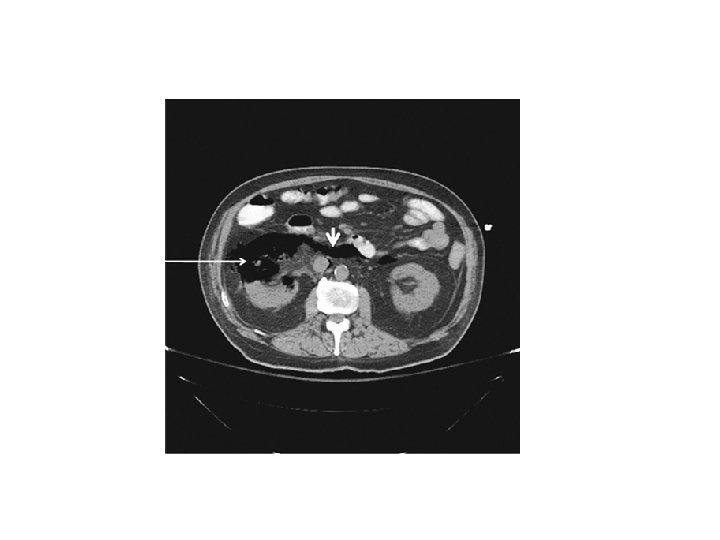

DIAGNOSIS • Plain film of abdomen / CT – air in the renal parenchyma, bladder, or surrounding tissue in 50 to 85% – CT scan, more sensitive than plain film extent of gas formation and any obstructing lesions in the urinary tract • Imaging, particularly CT scanning, classify emphysematous pyelonephritis to estimate prognosis & guide therapy

Prognostic classification • Two classification system , based upon CT scan finding • Type I : Renal parenchymal necrosis with absence of fluid collection or presence of streaky or mottled gas pattern Type II : Renal or perirenal fluid accompanied by bubbly gas pattern or gas in the collecting system Radiology 1996, 198, 433 -438. Type I EPN is associated with worse prognosis Mortality rate Type I 69 % VS Type II 18 %

Prognostic classification Class 1: Gas in the collecting system only Class 2: Gas in the renal parenchyma without extension to the extrarenal space Class 3 A: Extension of gas or abscess to the perinephric space, between the fibrous renal capsule and the renal fascia Class 3 B: Extension of gas or abscess to the pararenal space, space beyond the renal fascia and/or extension to adjacent tissue Class 4: Bilateral emphysematous pyelonephritis or solitary functioning kidney with emphysematous pyelonephritis Arch Intern Med 2000 Mar 27; 160(6): 797 -805.